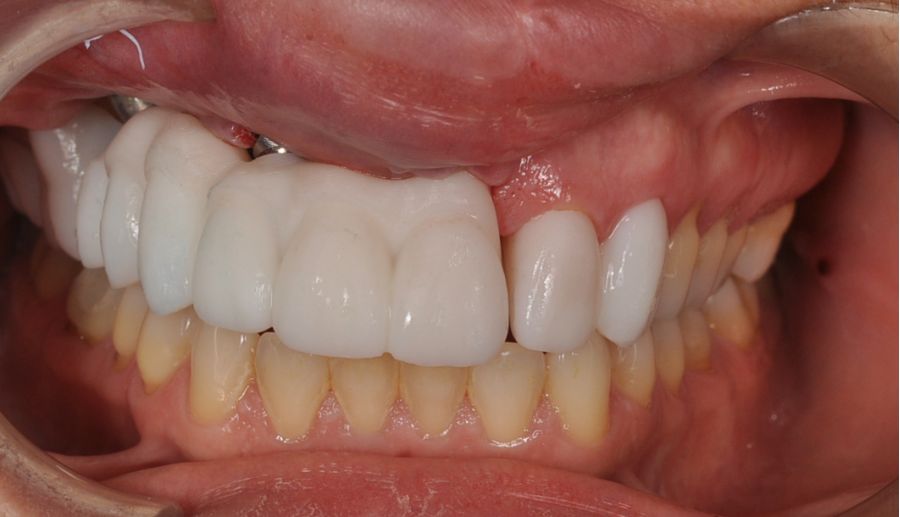

Una vez finalizada la radioterapia, la paciente se encontraba libre de enfermedad. Por lo que se procedió a la restauración definitiva implantosoportada. Tras la segunda fase, se colocaron dos pilares transepiteliales Multiunit Ò rectos y un pilar Multunit Ò angulado de 17º (Figura 10).

Para la fabricación de las estructuras, se eligió el óxido de zirconio monolítico como material restaurador sobre interfases metálicas en el puente implantosoportado, y coronas de óxido de zirconio monolítico en los dientes tallados previamente (1.7, 1.6, 2.2 y 2.3). Se tomaron impresiones de cubeta abierta con silicona de adición pesada y fluida (Zhermack Elite HD, Gmbh). Se realizó una prueba de pasividad analógica y el resto del proceso se confeccionó de manera digital, por lo que se hicieron pruebas estéticas de dientes impresas en 3D sobre interfases metálicas, para hacer todos los ajustes de función y estética previos al fresado del zirconio monolítico (Figuras 11, 12 y 13).

El día de la colocación de las estructuras, se arenó el interior de las coronas dentosoportadas con óxido de aluminio de 50 m y fueron cementadas con cemento de resina Multilink Ò. El puente implantosoportado se atornilló al torque indicado (20Nw) (Figuras 14, 15, 16 y 17).